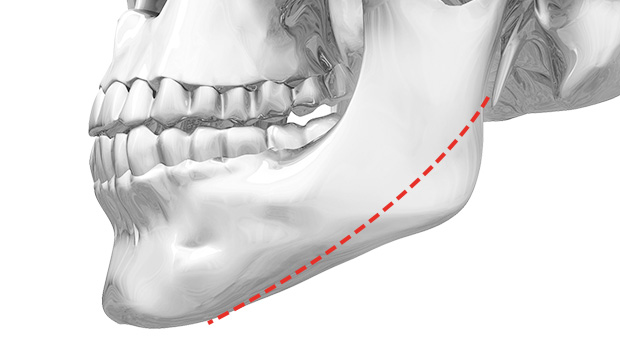

02. 長曲線方下巴縮小術

如果耳下方頜角切除過度,會變成不自然的“刀削臉”。

這是為什麼呢?因為耳下方頜角切除越多,會讓臉型越尖的錯誤想法所致。耳下方頜角與正面線條沒有直接關係。

耳下方頜角與耳垂距離維持在1.5cm左右,才更自然。另外,過度切除耳下方頜角容易產生二次角,這是因為截骨線的坡度不夠緩和。

WIAD長曲線方下巴縮小術在耳下保留1.5cm的自然距離,使下頜緣曲線柔美。